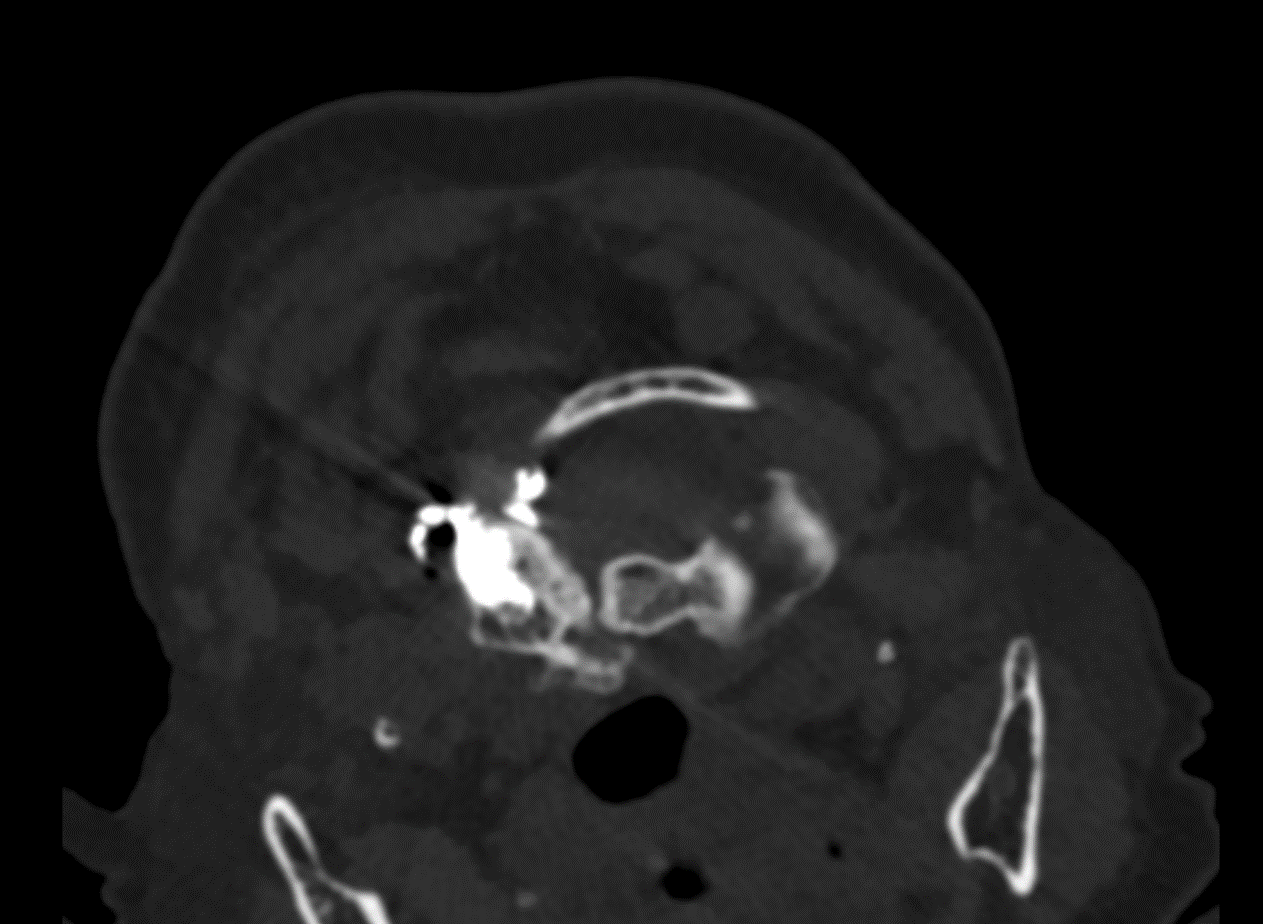

3月12日,疼痛科王立奎和陈家骅教授团队成功完成了一例老年患者的寰椎(第一颈椎)骨水泥注射术。患者为 80 岁女性,因“颈枕部疼痛8月加重2月余”就诊于我院疼痛科。患者表现为抬头后右侧后枕部疼痛明显。该患者每次下地活动20分钟后就必须平卧,正常生活起居受到极大影响。经检查患者系寰椎存在血管瘤占位,累及整个右侧寰椎侧块。

在完善相关检查后,团队采用自制的骨水泥注射针,在CT导航下完成了患者的寰椎骨水泥注射成形术。术后在王春霞护士长的护理团队的配合下,目前患者症状明显缓解,正常生活起居不再受限。患者对科室的治疗护理非常满意。

我院疼痛科自 2000 年开展该项技术以来,累计完成近3000例该类手术。与传统技术不同的是,科室采用的是CT导航下穿刺,能更清晰地显示椎体周围解剖结构,轴位成像使得上胸椎及颈椎的穿刺更具安全性和准确性。手术在局部麻醉方式下进行,对患者年龄及身体一般情况要求相对较低。且因为CT导航的精确性,骨水泥可精准注射到病变靶点,从而更安全更高效的解决患者不适症状。